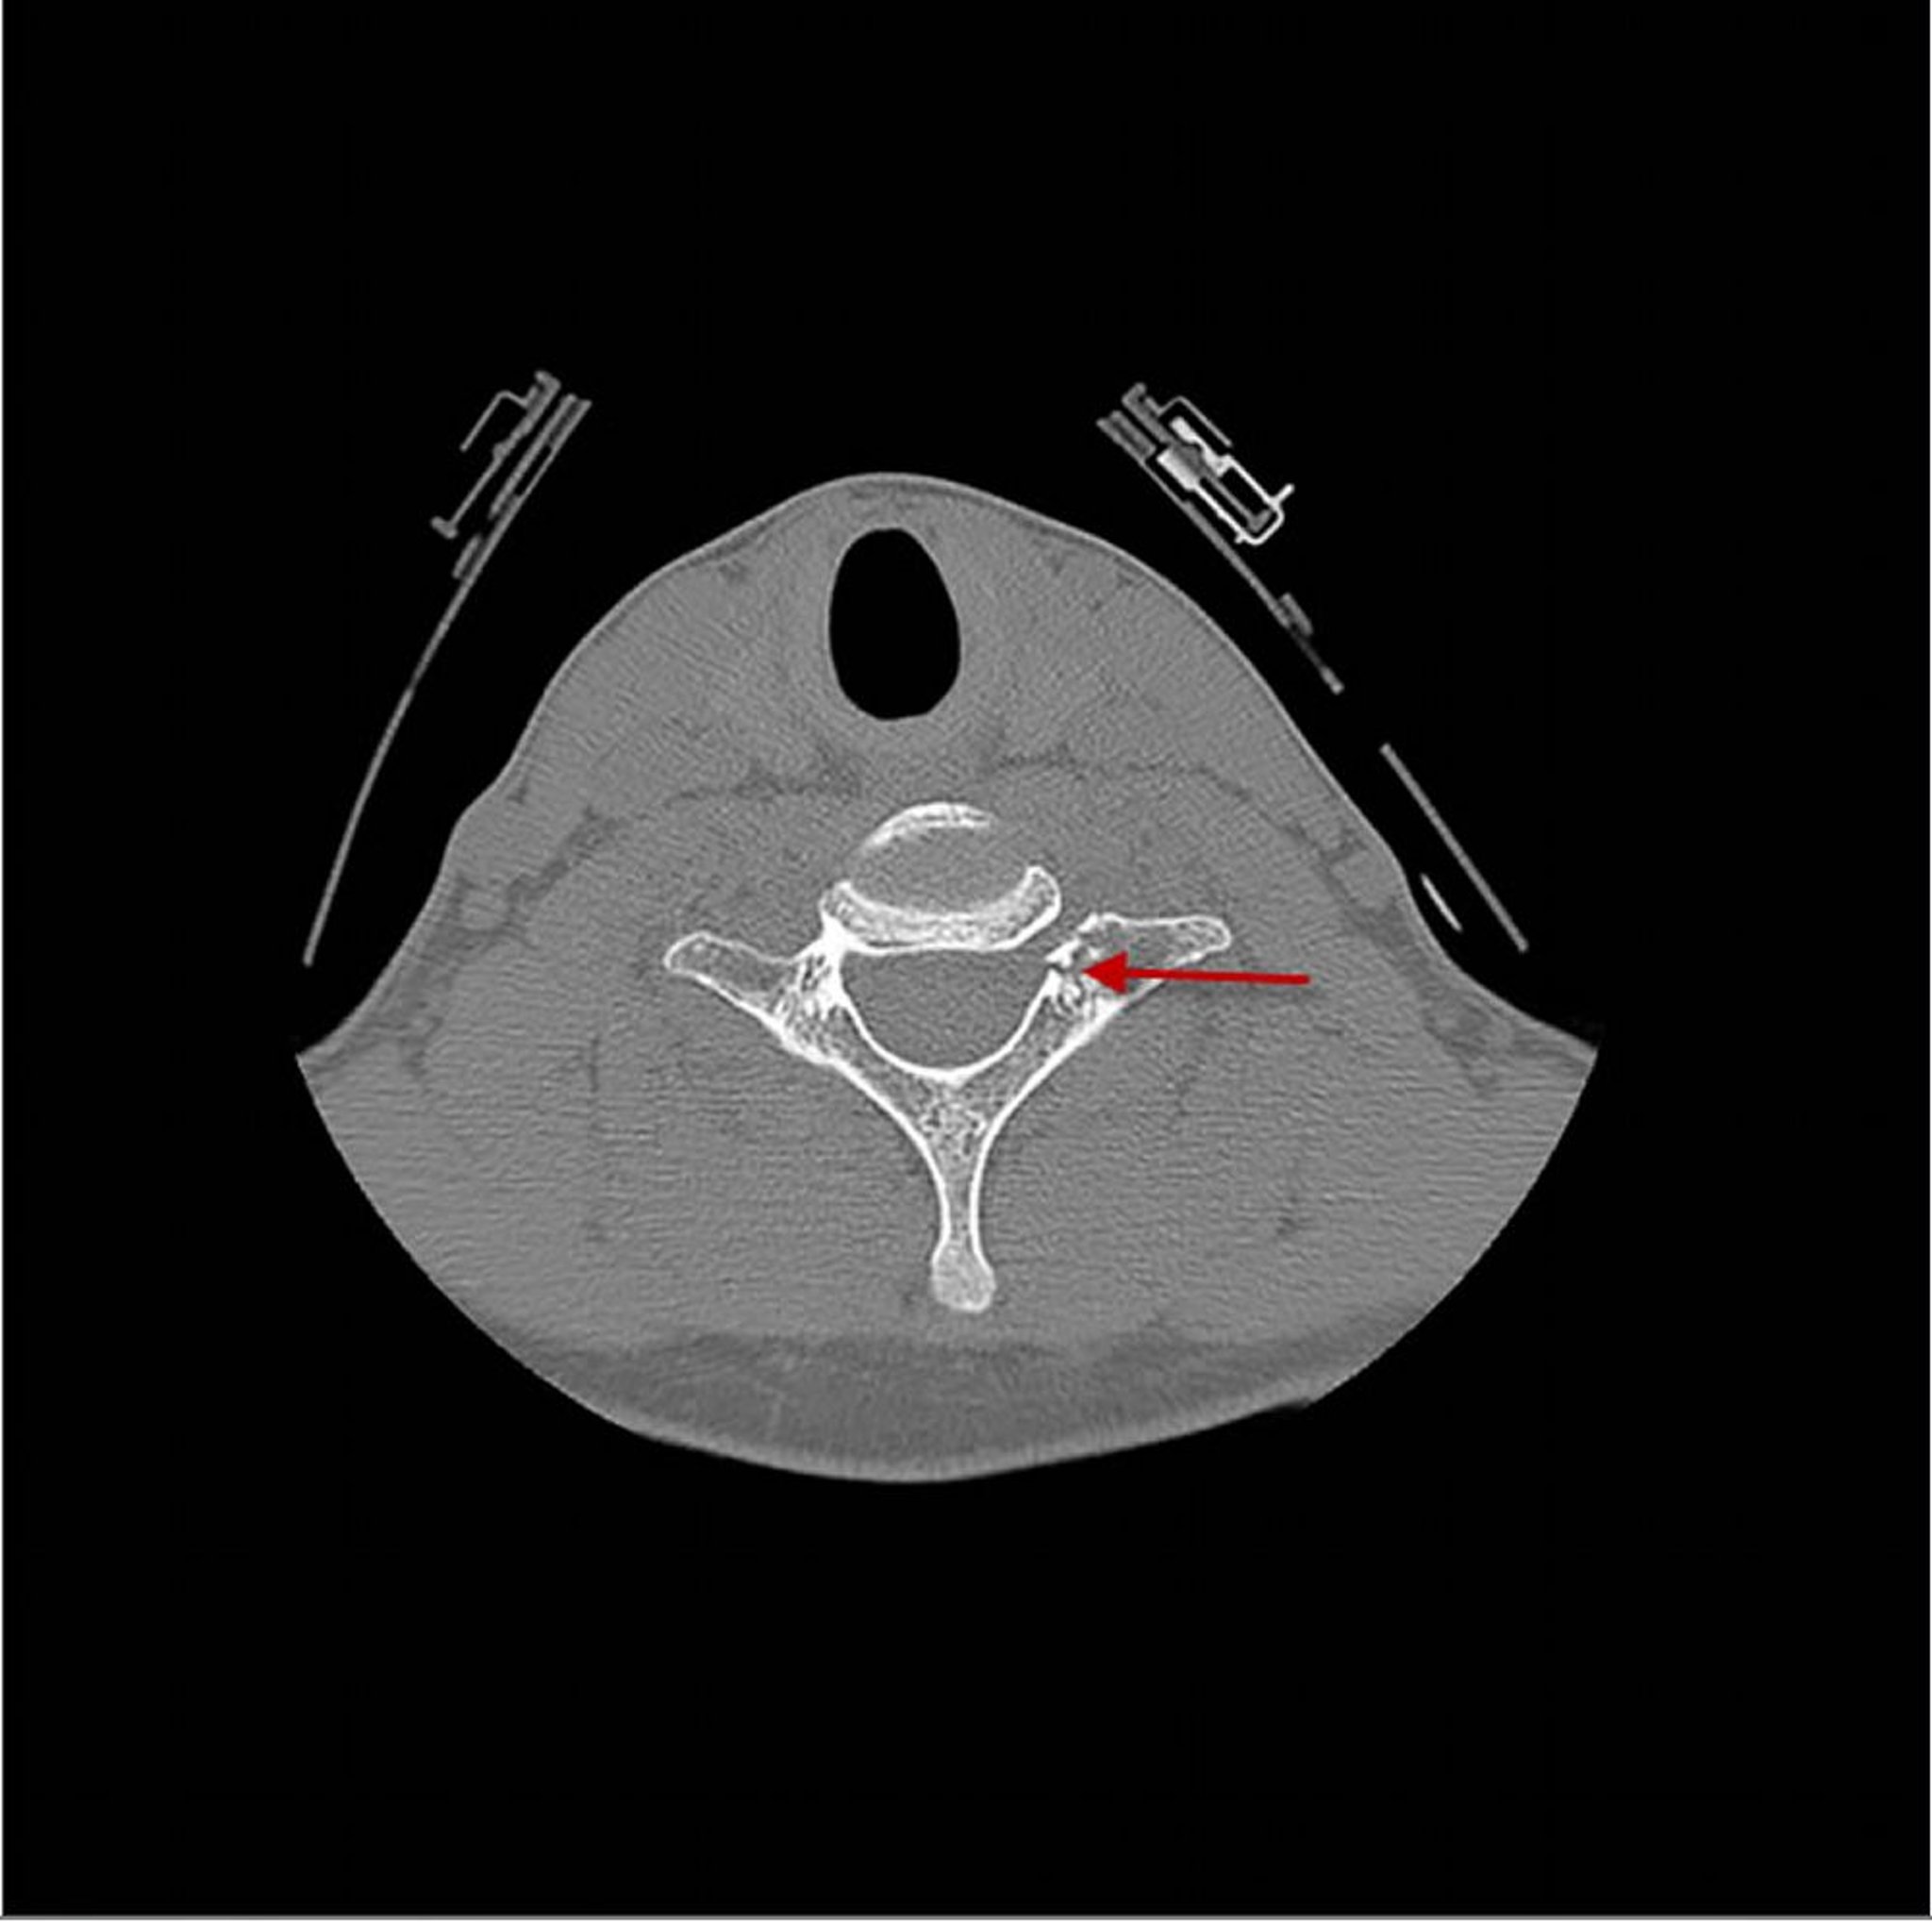

CT này cho thấy vết gãy (mũi tên) xuyên qua đốt sống cổ thứ 7 ngay sau thân đốt sống.

BÁC SĨ P. MARAZZI/THƯ VIỆN HÌNH ẢNH KHOA HỌC